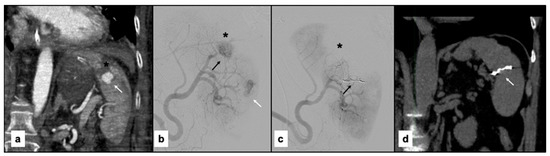

2.3. SAE Procedure

3.1. Embolization Technique and Agents Used